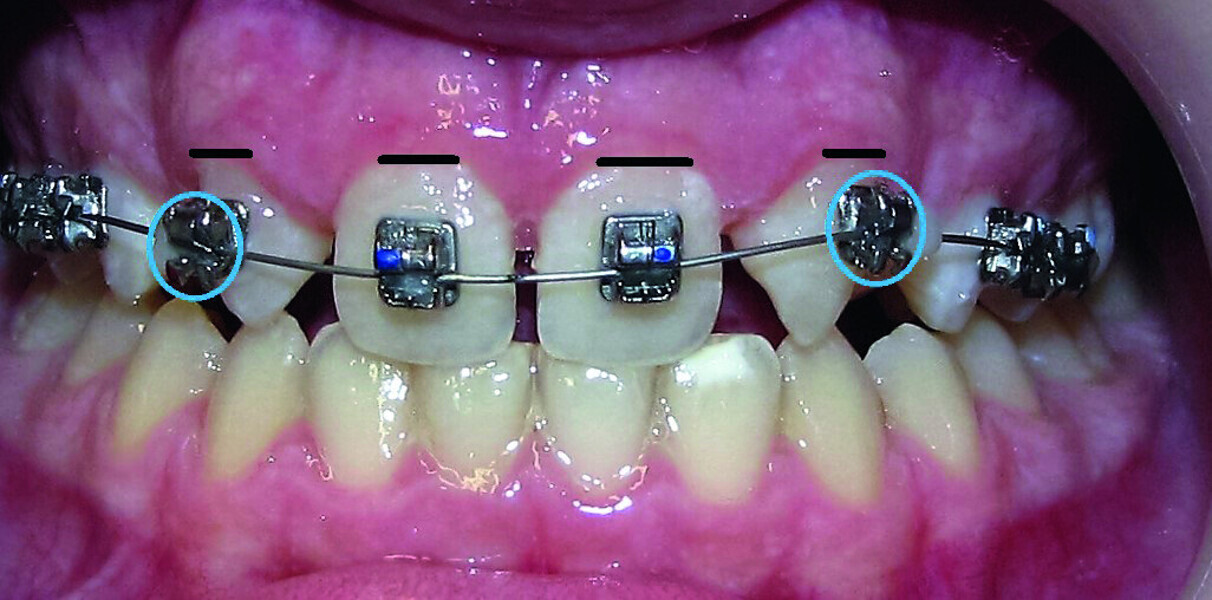

Orthodontic management of maxillary lateral incisors agenesis